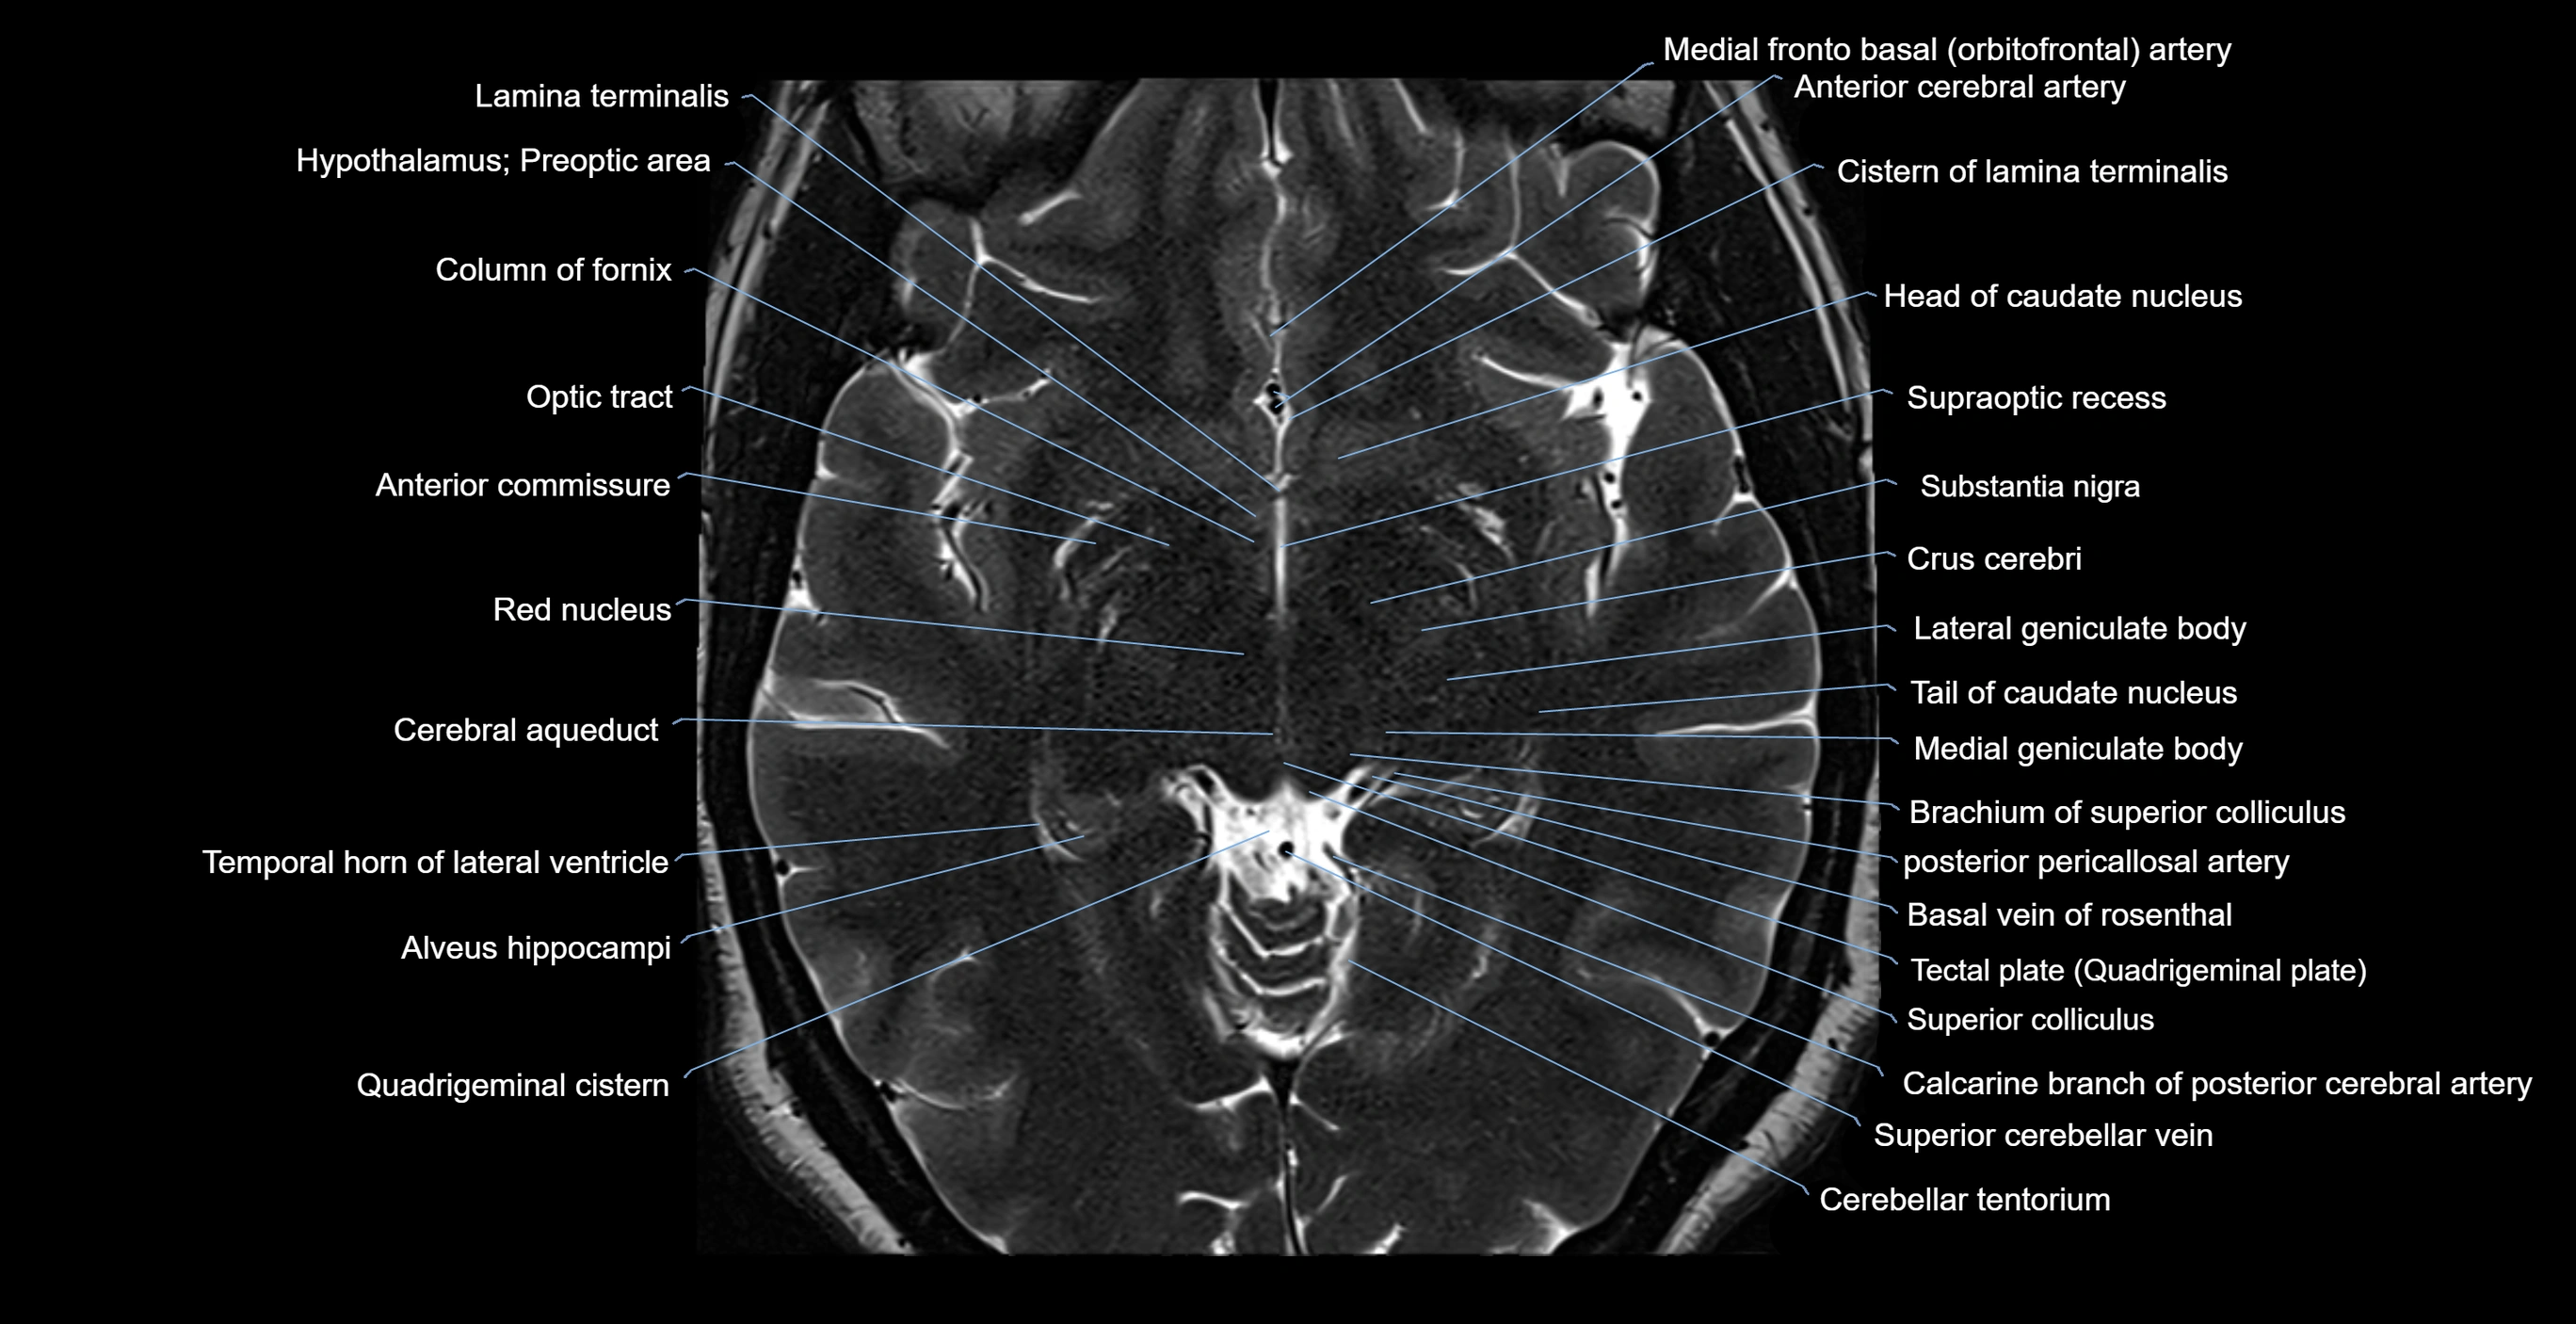

MRI images